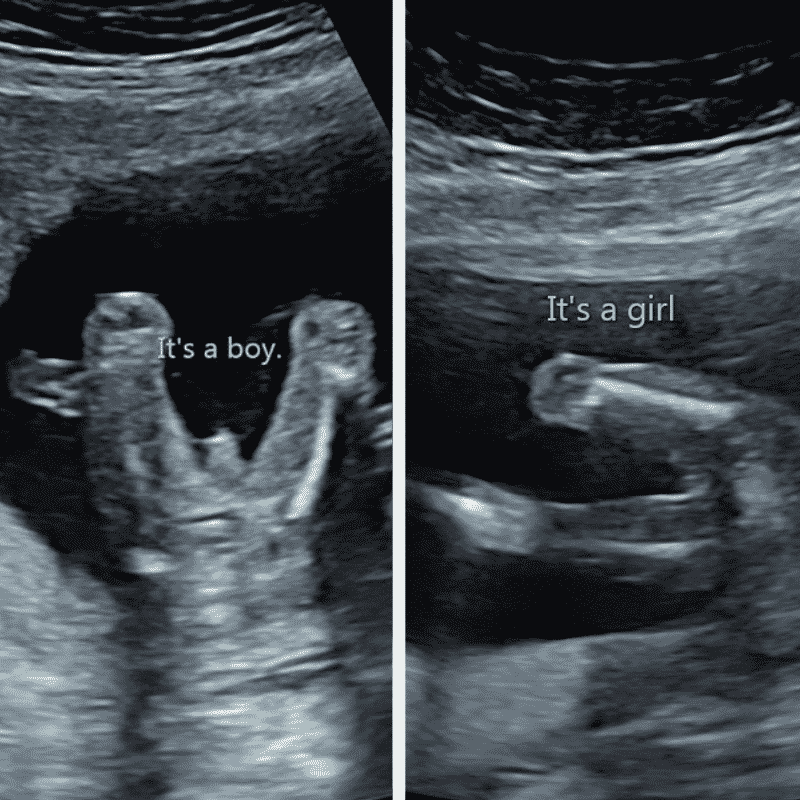

Below are ultrasound scans of slightly later stage babies. You can see the ‘boy genitalia’ on the left picture, and the renowned ‘three white lines’ on the right – a key indicator that you’re expecting a girl.